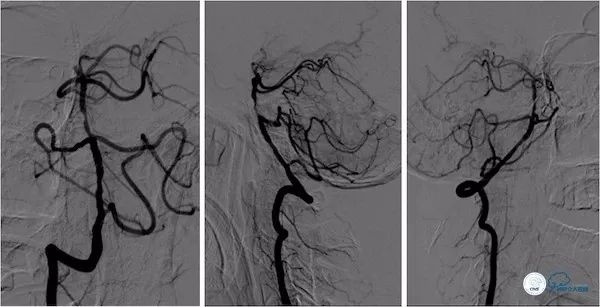

DSA:双侧颈动脉系统未见异常,双侧后交通动脉开放,右颈动脉造影可见基底动脉中上段显影。左椎动脉闭塞,右椎动脉V4段重度狭窄,基底动脉中段偏心重度狭窄(图5-8)。

图5

图6

图7

图8